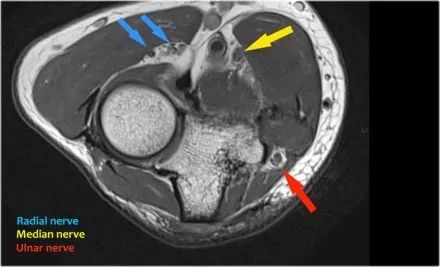

桡神经:在桡骨头水平可以最好地识别桡神经,在那里你可以看到桡骨隧道中的浅表和深支(箭头)。这是寻找桡神经的非常一致的地方。

深分支形成后骨间神经,穿过Frohse拱门(箭头)的旋后肌。

中位神经:正中神经落后于Lacertus纤维,即肱二头肌的腱膜并穿透旋前肌。